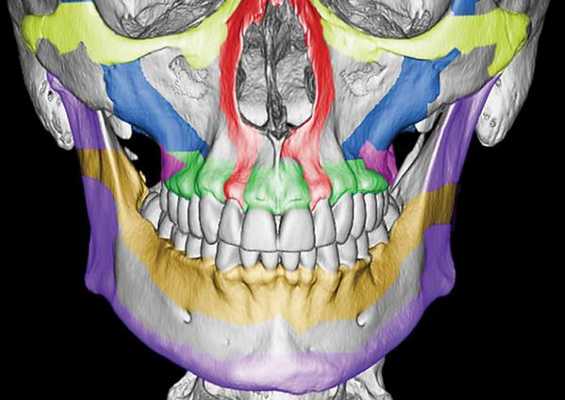

Чаще всего переломы классифицируют по Рене Ле Фору. Этот французский хирург систематизировал и описал формирующиеся повреждения костей средней зоны лица экспериментально: на головы свежих человеческих трупов он оказывал разные по направлению и силе воздействия по типу тупой травмы. Именно так и было обнаружено, что большинство линий переломов проходит по трём типам [1] :

- | тип — нижний, или горизонтальный тип, перелом Герена — Ле Фора. Перелом проходит над альвеолярным отростком и нёбным отростком через боковую и переднюю поверхности верхней челюсти, от крыловидных отростков основной кости к краю грушевидного отверстия.

- || тип — средний, или пирамидальный перелом, суборбитальный перелом. Линия перелома проходит через корень носа, внутреннюю стенку глазницы и далее — через нижнеглазничную щель кпереди по нижней стенке глазницы к месту альвеолярно-скулового контрфорса с переломом крыловидных отростков. Проще говоря, верхняя челюсть единым блоком "отсоединяется" от остальных костей средней зоны лица.

- ||| тип — верхний тип (поперечный, суббазальный, он же черепно-лицевое разъединение). Самый грозный вид перелома верхней челюсти, когда происходит отрыв верхней челюсти вместе со скуловыми костями от мозгового черепа. Как правило сочетается с тяжёлыми повреждениями головного мозга [3] .

Отличительные признаки каждого типа проявляются по уровню подвижности фрагментов, тяжести состояния больного и данным дополнительных методов исследования (компьютерной томографии).

Помимо классификации Ле Фора существует классификация переломов по Вассмунду, которая отличается лишь отсутствием в линии перелома костей носа. Различают также изолированные переломы отростков, поверхностей и частей верхней челюсти. Однако каждый челюстно-лицевой хирург, занимающийся травматологией, знает, что в жизни всё происходит не совсем так, как написано в книгах. Очень часто верхняя челюсть ломается по другим схемам. Поэтому, готовясь оперировать пациента, хирурги сталкиваются с очень трудоёмкой задачей — им необходимо понять, как собрать этот многооскольчатый "конструктор" с максимальным восстановлением анатомии и функции челюсти через минимальные разрезы с минимальным нарушением кровоснабжения и максимальной стабильностью.